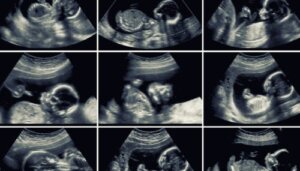

Med hjälp av ultraljud sker vid vecka 20 ett rutintest som möjliggör en grundlig utvärdering av barnets organ, moderns livmoder och moderkakan. Förutom den värdefulla informationen den ger utförs den vid ett avgörande ögonblick under graviditeten.

På så sätt kan läkaren utvärdera hur barnet växer och utvecklas inuti livmodern. Och samtidigt möjliggör ett ultraljud vid vecka 20 en tidig upptäckt av eventuella anomalier då det kommer till utvecklingen av barnets kroppsdelar och organ.

Vid den ultraljudsundersökning som sker analyseras barnets morfologi i detalj för att upptäcka eventuella problem i dess organ och vävnader så tidigt som möjligt. Dessutom bekräftar undersökningen tillståndet hos moderkakan, navelsträngen och moderns könsorgan.

I allmänhet är detta ultraljud 2D. Men om enheten tillåter det kan vissa bilder tas i 3D eller 4D. Den senare visar barnets ansiktsdrag med större precision och visar till och med dess rörelser i realtid.

Specialisten kan kombinera 2D- och 3D-bilder för en mer komplett analys av alla bebisens strukturer.